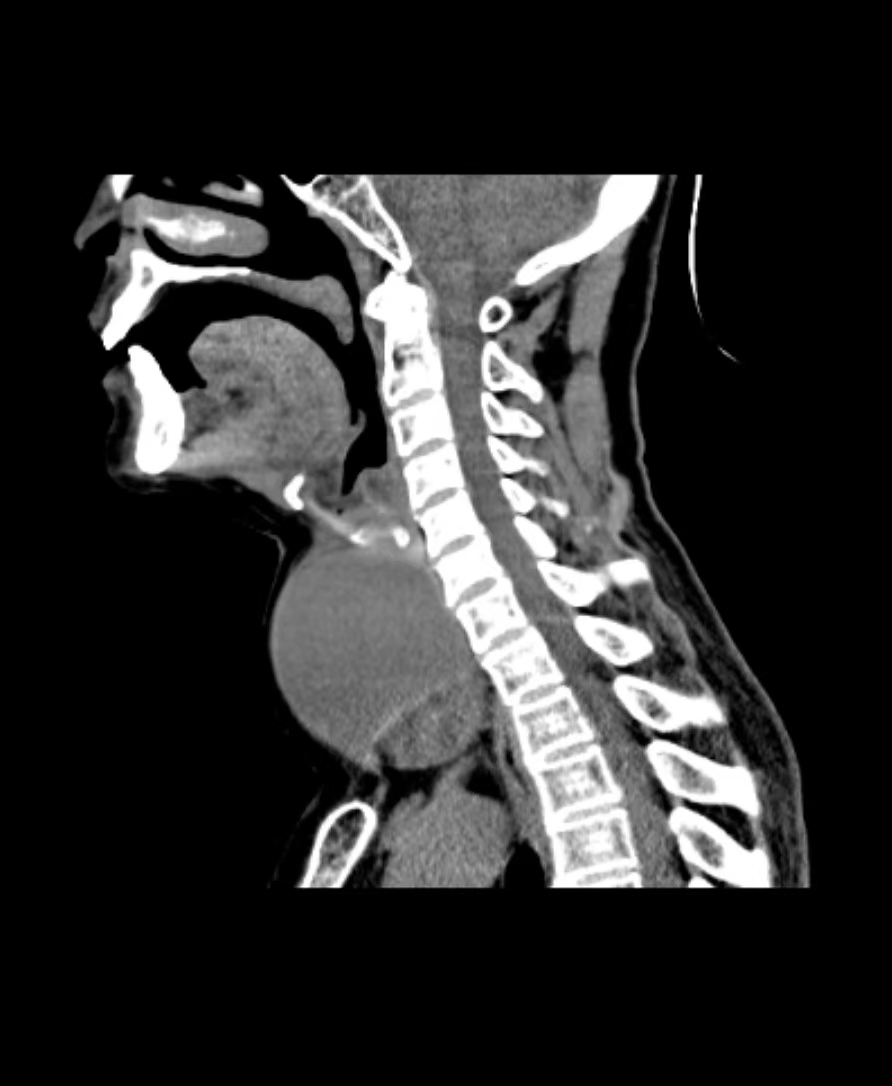

入院后的检查结果让医生皱起眉头,肿瘤直径达到7.4cm,充斥着整个脖前,并与颈部重要血管、神经紧密粘连,更棘手的是,部分瘤体已坠入胸骨后。在这种情况下手术,稍有不慎,就可能损伤喉返神经导致永久性声音嘶哑,或损伤甲状旁腺导致终身手足抽搐。

但手术是唯一的选择。再拖下去,肿瘤继续增大,随时可能压迫气管导致窒息。